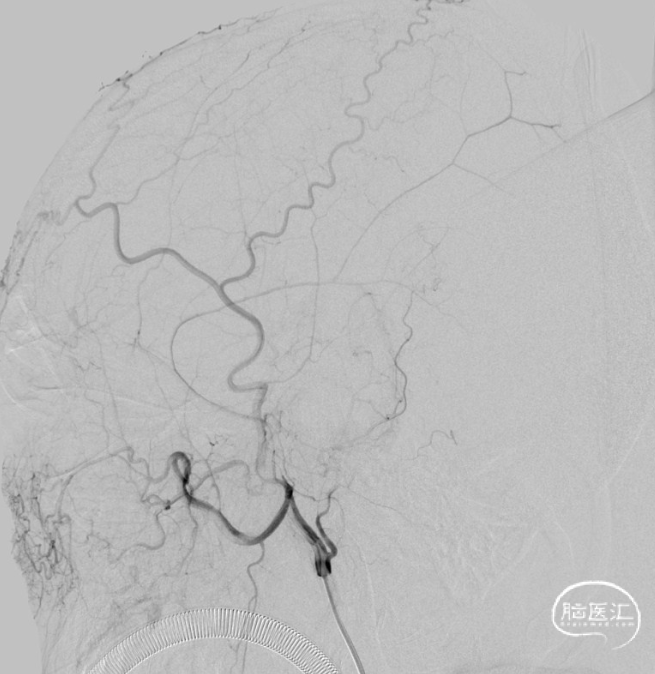

一期治疗

治疗经过